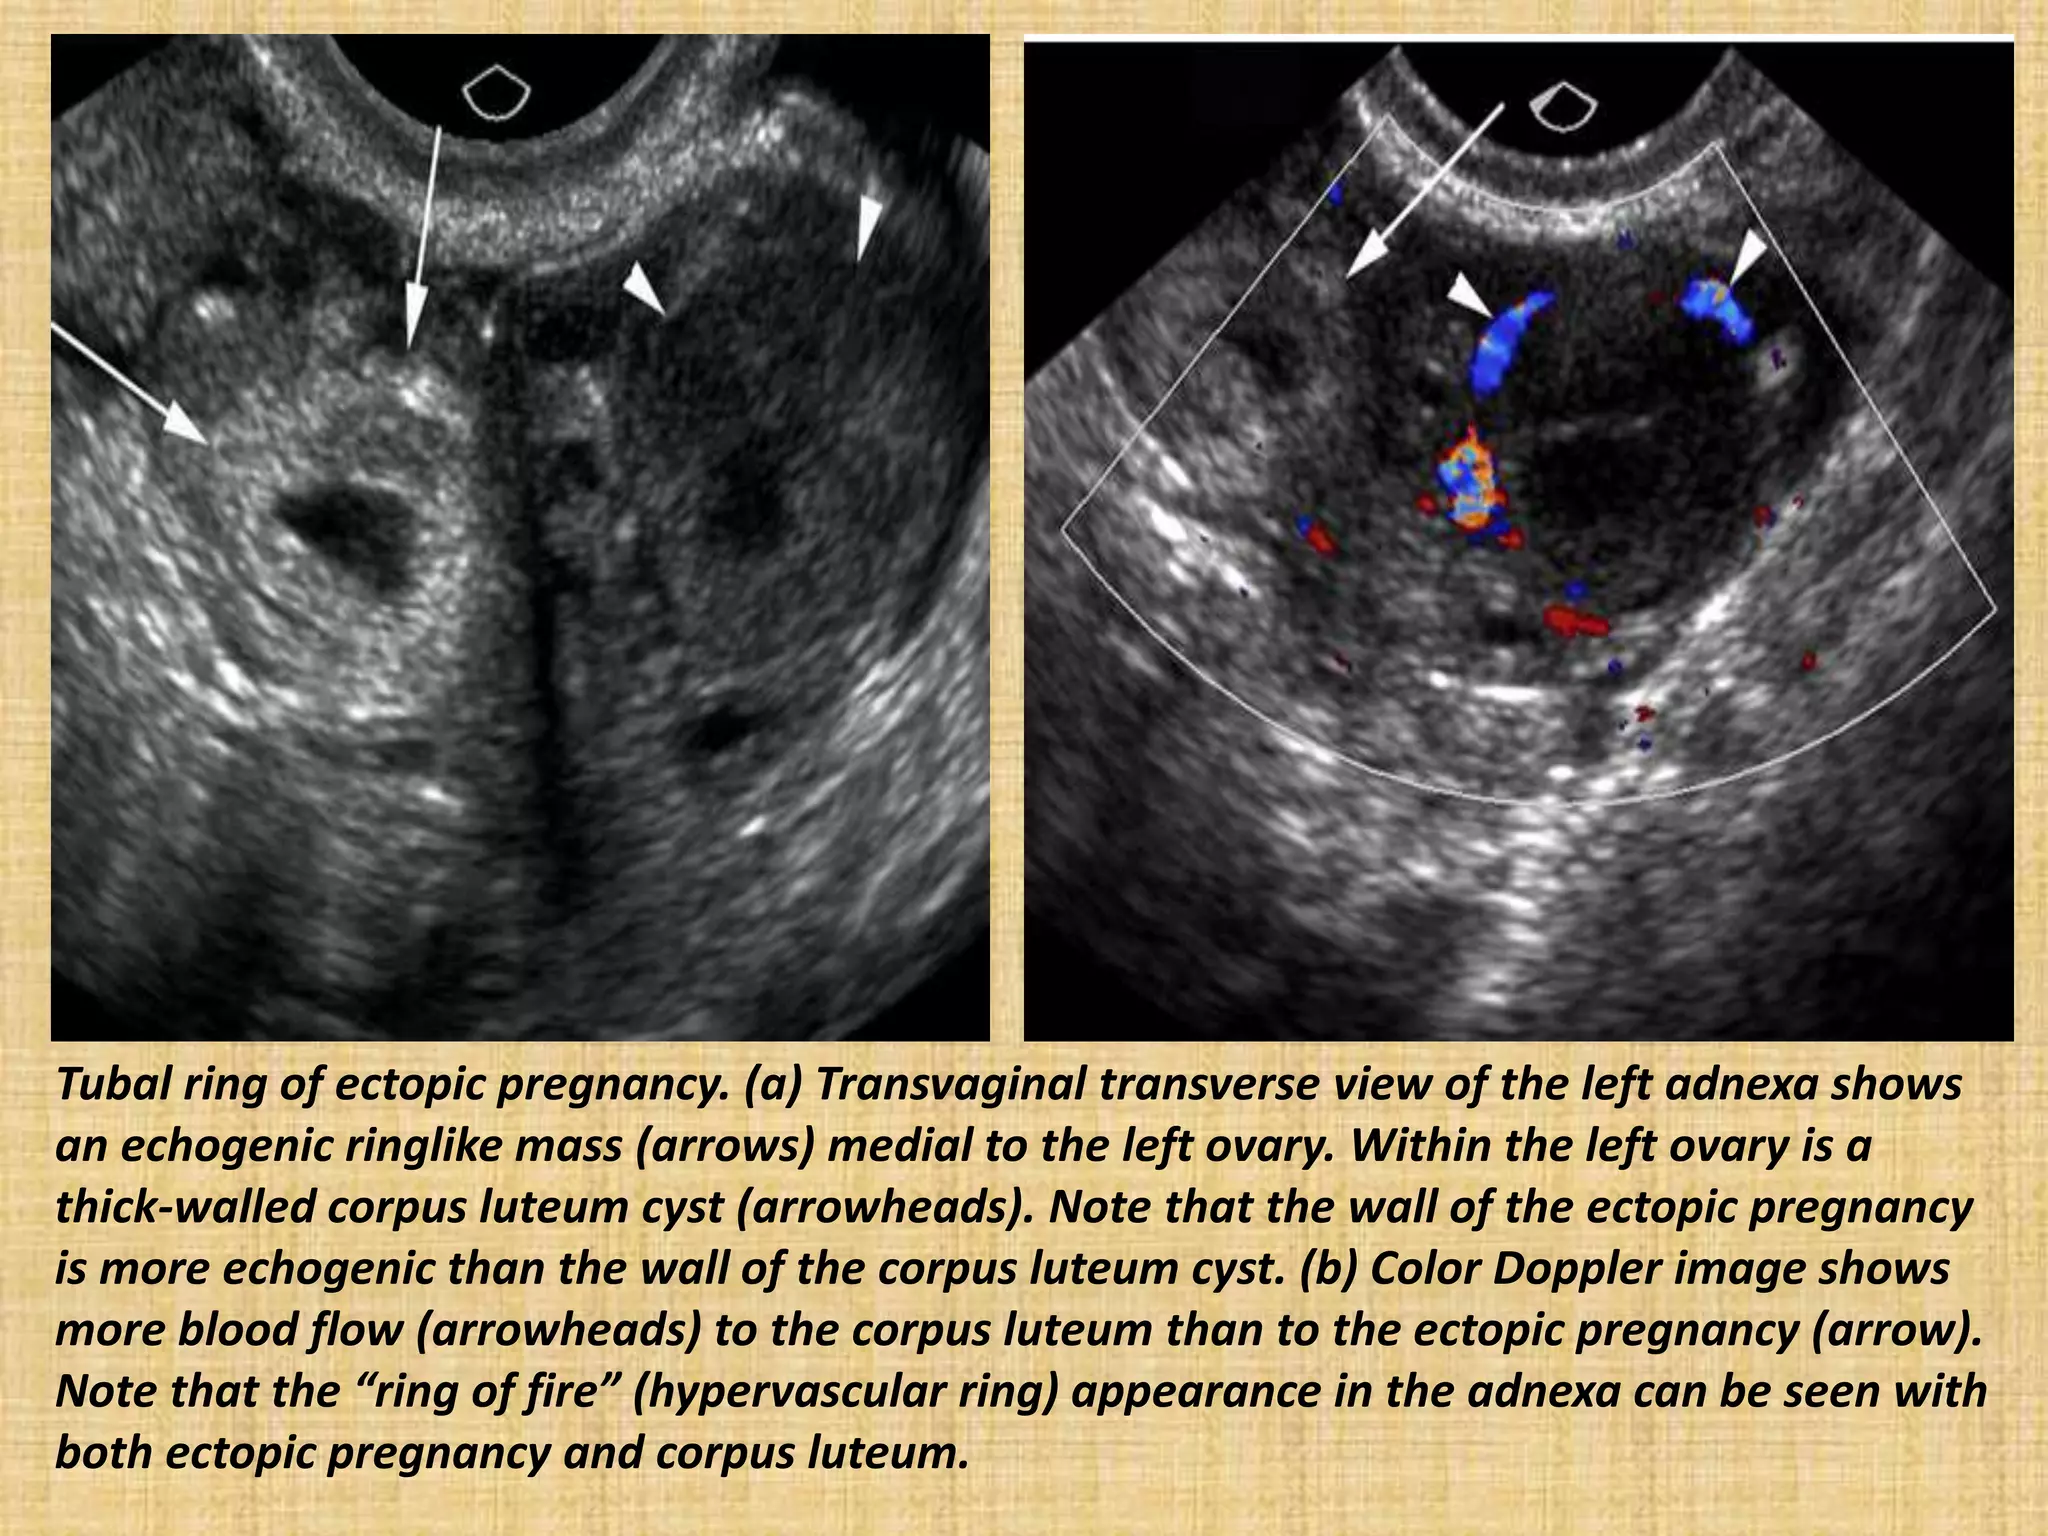

Tubal ring of ectopic pregnancy. (a) Transvaginal transverse view of the left adnexa shows

an echogenic ringlike mass (arrows) medial to the left ovary. Within the left ovary is a

thick-walled corpus luteum cyst (arrowheads). Note that the wall of the ectopic pregnancy

is more echogenic than the wall of the corpus luteum cyst. (b) Color Doppler image shows

more blood flow (arrowheads) to the corpus luteum than to the ectopic pregnancy (arrow).

Note that the “ring of fire” (hypervascular ring) appearance in the adnexa can be seen with

both ectopic pregnancy and corpus luteum.

Tubal ring ofectopic pregnancy. (a) Transvaginal transverse view of the left adnexa shows an echogenic ringlike mass (arrows) medial to the left ovary. Within the left ovary is a thick-walled corpus luteum cyst (arrowheads). Note that the wall of the ectopic pregnancy is more echogenic than the wall of the corpus luteum cyst. (b) Color Doppler image shows more blood flow (arrowheads) to the corpus luteum than to the ectopic pregnancy (arrow). Note that the “ring of fire” (hypervascular ring) appearance in the adnexa can be seen with both ectopic pregnancy and corpus luteum.